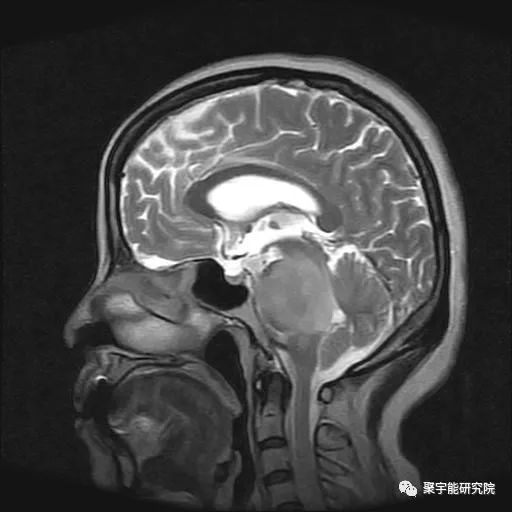

脑部胶质瘤

脑癌的特点从纯中医角度看,是脑子里的废水太多了,将废水除了,何来脑癌之有?如何除去脑子里的废水?